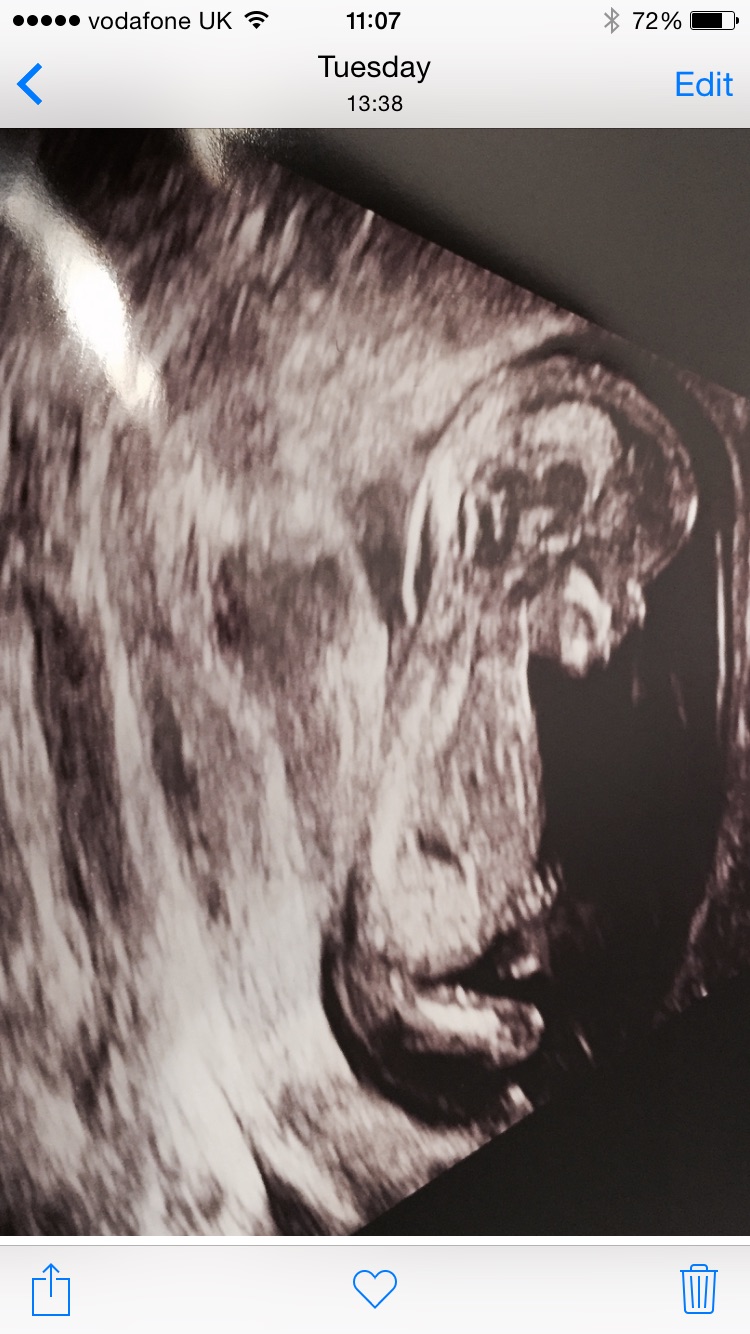

Does anyone have a clue what I'm having (other than a baby!)...

Attachment 24271Attachment 24272

Maybe Girl if 13 weeks or more :)

Was 13+ 1 at the time

I think there's a bit of an angle on the nub, BUT looks like a girly shape. Thinking boy 75/25

Boy lean due to slight angle from me.

This is a hard one! Boy lean as slightly raised and quite a short nub X